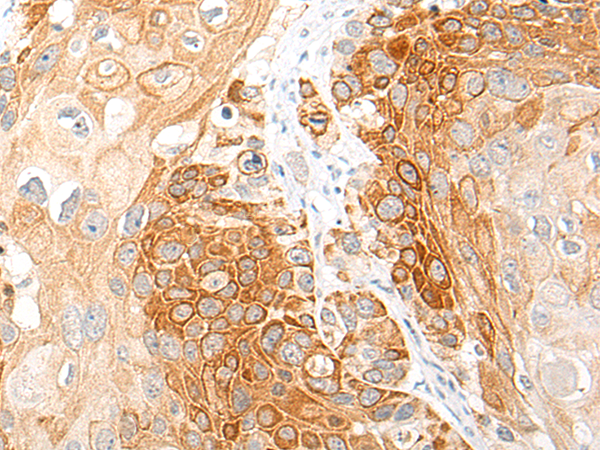

分类: 科研抗体货号: P13200别名: CLL1; MICL; CD371; CLL-1; DCAL-2应用: IHC反应种属: Human